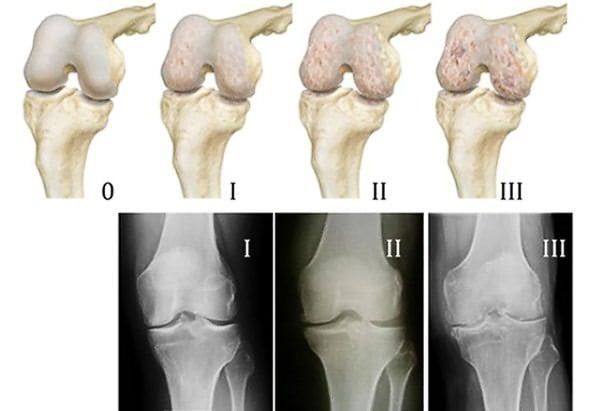

На начальном этапе развития заболевания повреждается хрящевая прослойка, выстилающая поверхности костей. Она истончается, уплотняется, перестает выполнять свою основную амортизирующую функцию. Теперь хрящ не гладкий и упругий, а шершавый, с множеством радиальных трещин на поверхности. При смещении образующих сустав костей хрящевые структуры цепляются друг за друга, что приводит к еще большему их разрушению.

Постепенно деформируются костные поверхности, которые разрастаются с образованием острых наростов — остеофитов. Костные шипы при смещении травмируют мягкие ткани, провоцируя развитие воспалительного процесса. В него вовлекаются синовиальная оболочка, суставная сумка, связки, сухожилия.

- Для артроза коленного сустава характерна быстрая деформация. Разрушение хрящевой ткани при постоянных нагрузках на сустав приводит к появлению шипов, остеофитов, наростов. Колено постепенно перестает сгибаться, а отек и сильная боль мешают наступать на ногу.

Разница в рентгенологических картинах:

- при артрозе плотность костной ткани повышается (остеосклероз), по краям суставных площадок образуются наросты-остеофиты, на фоне остеосклероза возможны единичные кистоподобные полости, окруженные склерозированным ободком;

- при артрите плотность кости уменьшается (остеопороз), формируются краевые дефекты костной ткани и множественные кисты.

Если данные лабораторных анализов указывают на артрит, а рентгенологическая картина характерна скорее для артроза, но имеет нетипичные черты, диагностируют артрозоартрит. В МКБ 10 такого заболевания нет, данный диагноз используется только в клинической практике.